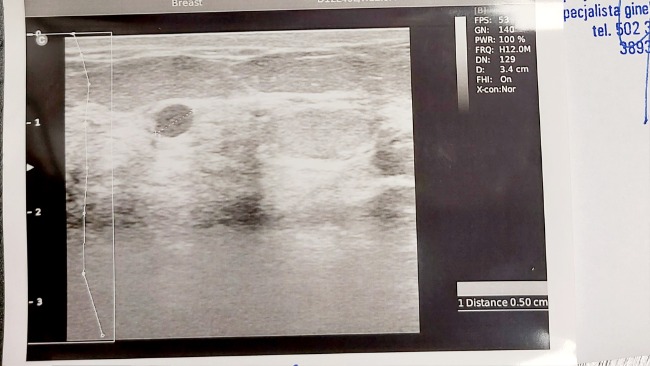

Ze złośliwym rakiem piersi zaczęłam walkę w 2019roku, w wieku 49lat, diagnoza rak in situ nieznanego typu Birads 5 ....

Pól roku po zakończonej chemioterapii raka piersi pojawiły się podskórne guzki na implancie zrekonstruowanej piersi, które po wycięciu w maju 2021r potwierdziły wznowę.

Jednak zaraz po powrocie 22 października 2021 podczas samobadania wyczułam kolejny guzek, w tej samej operowanej piersi. Znowu nerwy, kolejna seria badań i kolejna operacja - mastektomia radykalna + węzły. Wynik hispatologiczny nowy typ raka.

RAK DWUOGNISKOWY

Rak duogniskowy złośliwy.